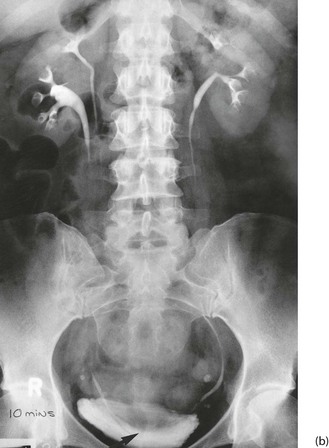

Fig. 39.1 Polycystic kidneys

IVU tomogram from a 52-year-old woman with hypertension and microscopic haematuria; both kidneys exhibit multiple lucent areas in the nephrogram representing cysts (arrowed) and the pelvicalyceal systems are slightly compressed